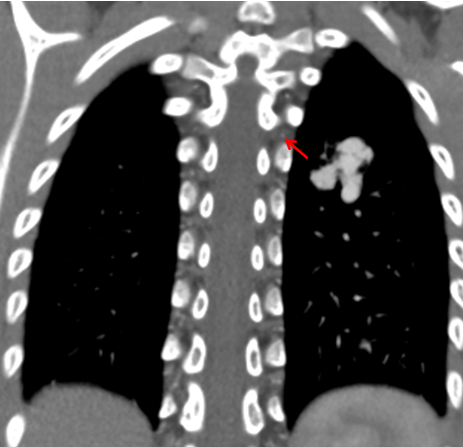

6歲的夕夕(化名)在查體時發(fā)現(xiàn)了肺上長了一團(tuán)迂曲增粗的異常血管影。雖然孩子除了活動耐力略差外,其他方面看起來一切正常,出于謹(jǐn)慎考慮,夕夕媽媽還是帶著孩子來到了青島婦兒醫(yī)院。血管瘤&脈管畸形??漆t(yī)師接診后對孩子進(jìn)行了相關(guān)檢查,診斷夕夕患有“肺動靜脈瘺”!

肺動靜脈瘺是一種較為嚴(yán)重的先天性肺血管畸形,早期大多沒有明顯癥狀,但隨著年齡增長,病情進(jìn)一步進(jìn)展,可逐漸出現(xiàn)呼吸困難、心慌、氣短、紫紺、胸痛、咯血等癥狀,甚至可以出現(xiàn)腦梗塞、腦膿腫等嚴(yán)重并發(fā)癥,危及生命!